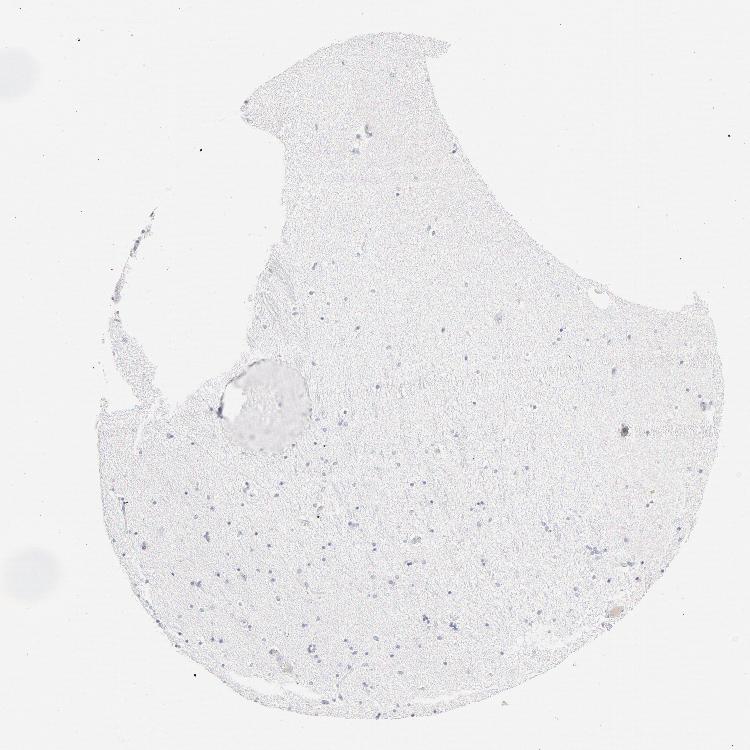

HIPPOCAMPUS - Antibody stainingi

Antibody staining in the annotated cell types in the current human tissue is reported as not detected, low, medium, or high, based on conventional immunohistochemistry profiling in selected tissues. This score is based on the combination of the staining intensity and fraction of stained cells.

Each image is clickable and will lead to virtual microscopy that enables deeper exploration of all samples and also displays staining intensity scores, fraction scores and subcellular localization as well as patient and tissue information for each sample.

Antibody HPA003898Antibody CAB002163Antibody CAB016312

Glial cells Not detectedNot detectedNot detected

Neuronal cells Not detectedNot detectedNot detected